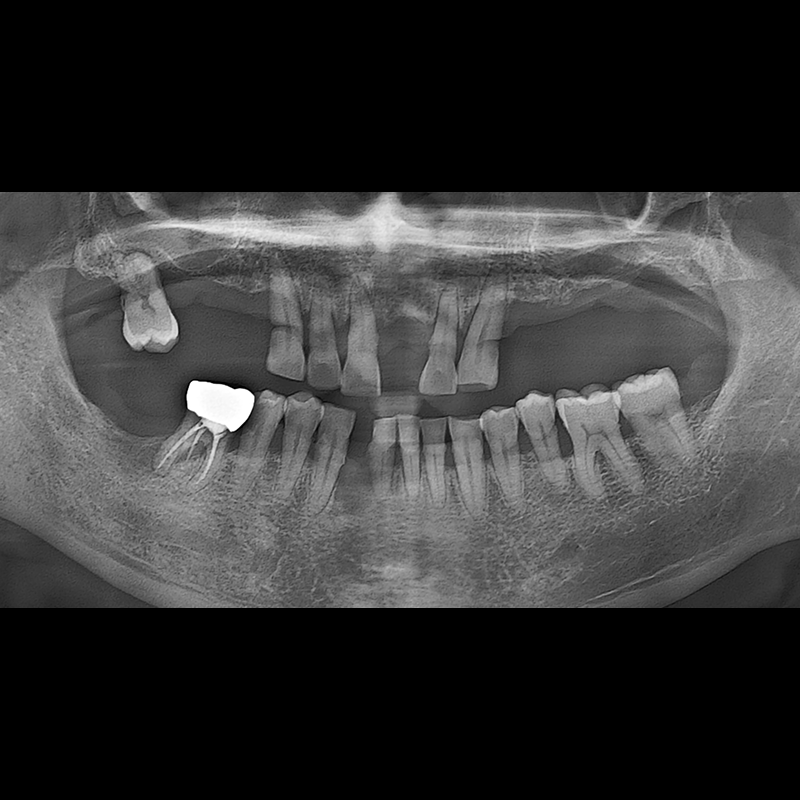

BEFORE AFTER

种植牙前后的照片 2025.05.30

在缺失的牙齿部分和难以挽救的牙齿位置植入了种植牙。